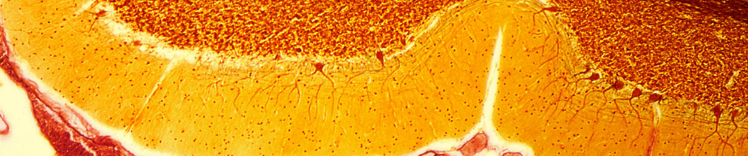

CÉLULAS DE PURKINJE EN EL CEREBELO